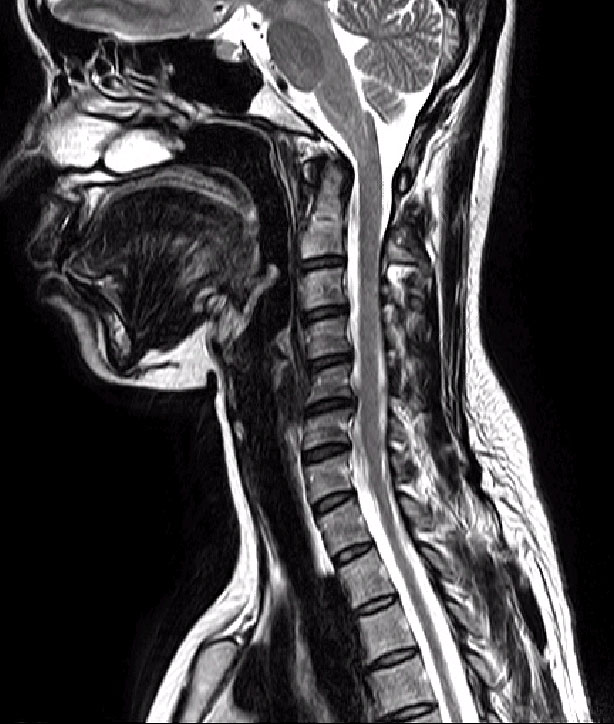

йڻ̸ ̽ ̽ʴϴ. ص帮 ȸ̵may28 1C.ٸǷ, 6C.ڸ , 6C. κ Ḳ , 6C.ھ Ḳ , 6C.ڻ , Ͻ йڻ, ̸, Ƴ ȣ ȣ ȰϿ ǷԴϴ. Ƴ εũ ȣ ȵǾ ġῡ ǰ ǥغ ֹ 帳ϴ. Ƴ Ұ MRI Ͽ 帮 ǰ ; ϵ帳ϴ. Ƴ 2 cervival HIVD 5,6 ȿ numbness, painful sensation ȣϿ, Ƿ Ȱа, ġ ȣǾ, 2008 5 ٽ , ó ܰ ġ Ͽ ȣ, ô MRI Cervical HIVD 5.6.7 ǸǾ, FIMS(MRI ų Ǵ ãƼ , ̵ ȥ Ͽ ȭŰ Ű ڱ ִ ġ)2ȸ Ͽ ȣ, ġḸ ̸, 3ȸ FIMSġص ȣ ġ(ΰũ Լ) Դϴ. |